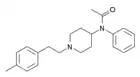

- Part III

The modifications described here cover alterations to the ring structure donated by the fentanyl precursor 4-ANPP. Although another series covered substitutions of hydrogen atoms on the original carbon ring structure, sometimes called functional group additions, this series focuses on the three main modifications to the phenethyl moiety. The first modifications is the removal of the phenthyl moeity from the piperidinyl nitrogen, depicted here as hydrolysis yielding phenethanol. This changes the parent skeletal name to norfentanyl.

The second and third modifications are the removal and addition of a methylene moiety internally in the ethyl chain within the greater phenethyl moiety. The removal of a methylene, which shortens the chain by one carbon length, creates the benzylfentanyl structure. The addition of a methylene, which lengthens the chain by one length, creates homofentanyl.